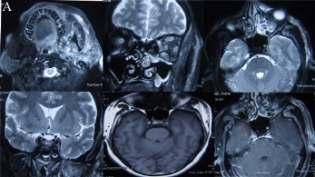

Emphysematouspyelonephritis–inanon-diabeticyoungwomen

—arareassociation— Y S Ravikumar, K M Srinath, L S Adarsh, Manjunath S Shetty, Subrahmanyam Karuturi, B Balaji Kirushnan .................................................108 Rhinocerebralmucormycosis:reportoftwocasesandreviewofliterature — Gopee E Makwana, Vikash Jain, Nandini Bahri, Mala Sinha, Manish Kumar Mathur.................110 Harlequinichthyosis—acasereport— Sendhil Coumary A, Seethesh Ghose .................................113 ..............................................................................................................................................116